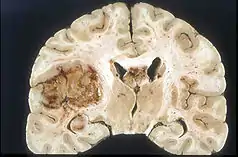

![]() Glioblastoma arising in an astrocytoma. This spinal cord exhibits both a lightly staining microcystic astrocytoma as well as a darkly staining glioblastoma. | |